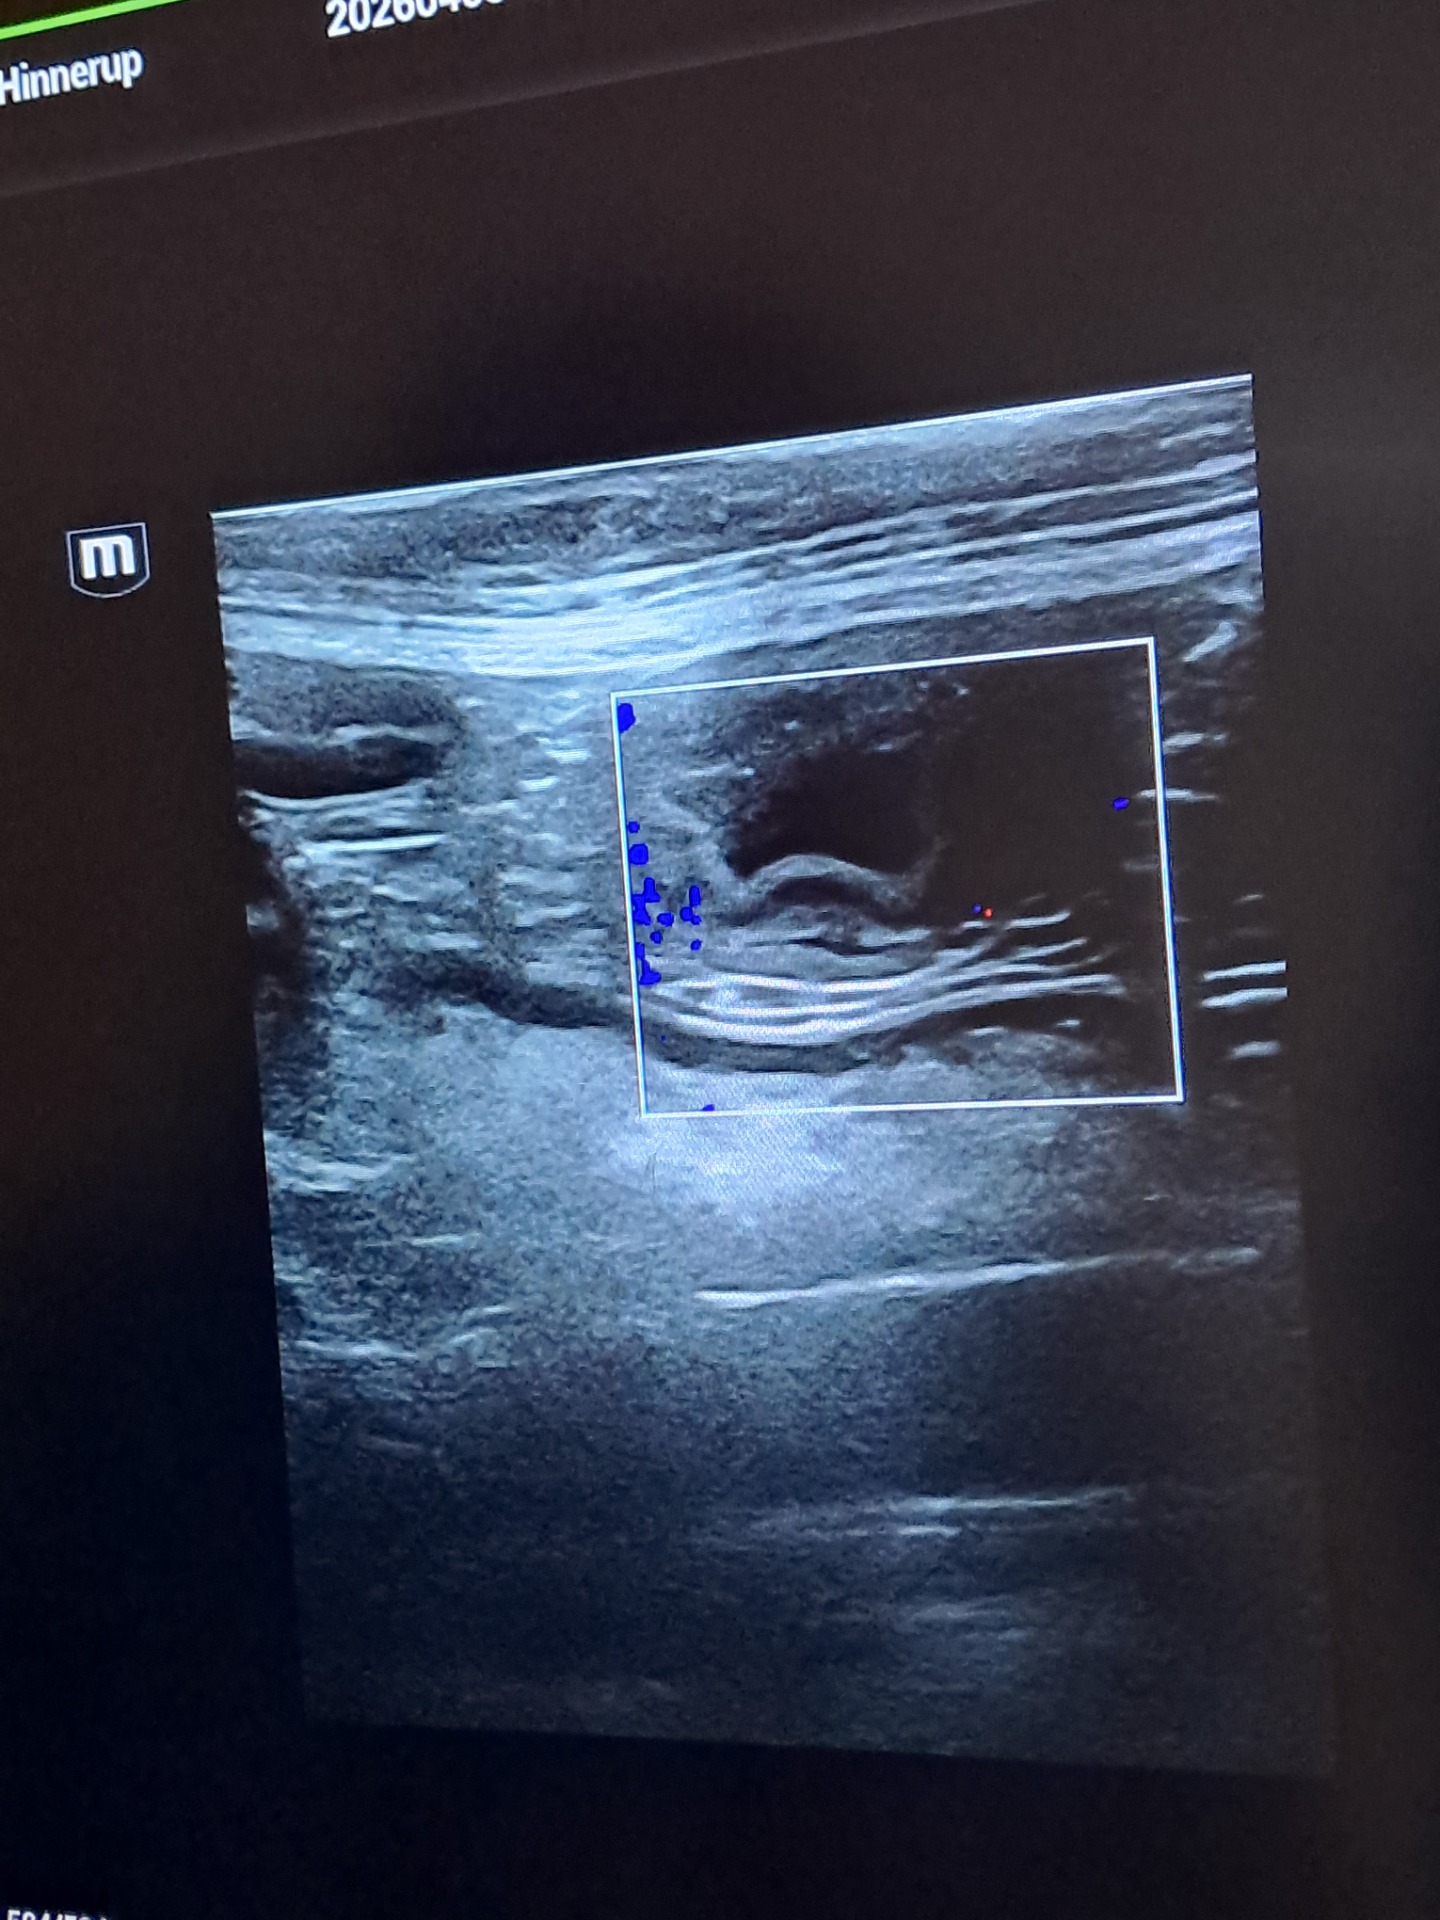

Catja er parret med Mac di Riviera Italia d 15/3.26 termin d 17/5.26